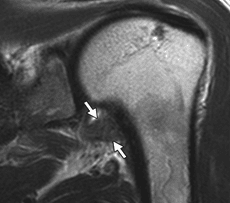

Diagnosticul paraclinic – examinarea radiologică a șoldului ne poate arăta în faze mai avansate modificări de structură ale capului femural, colapsul acestuia și, în stadiul final, degenerarea întregii articulații. Examinarea RMN este investigația paraclinică de elecție în cazul acestei patologii, putând face diferența între osul sănătos, edemul osos și osul deja necrozat. Examinarea CT evidențiază cu acuratețe mai mare dacă suprafața osoasă a capului femural s-a prăbușit, fiind necesară pentru diferențierea anumitor stadii de evoluție.

Imagini RMN care evidențiază necroza capului femural; imaginea din partea dreaptă – efectuare foraje cap femural.

Examinare RMN – necroză cap femural drept, cap femural stâng sănătos.